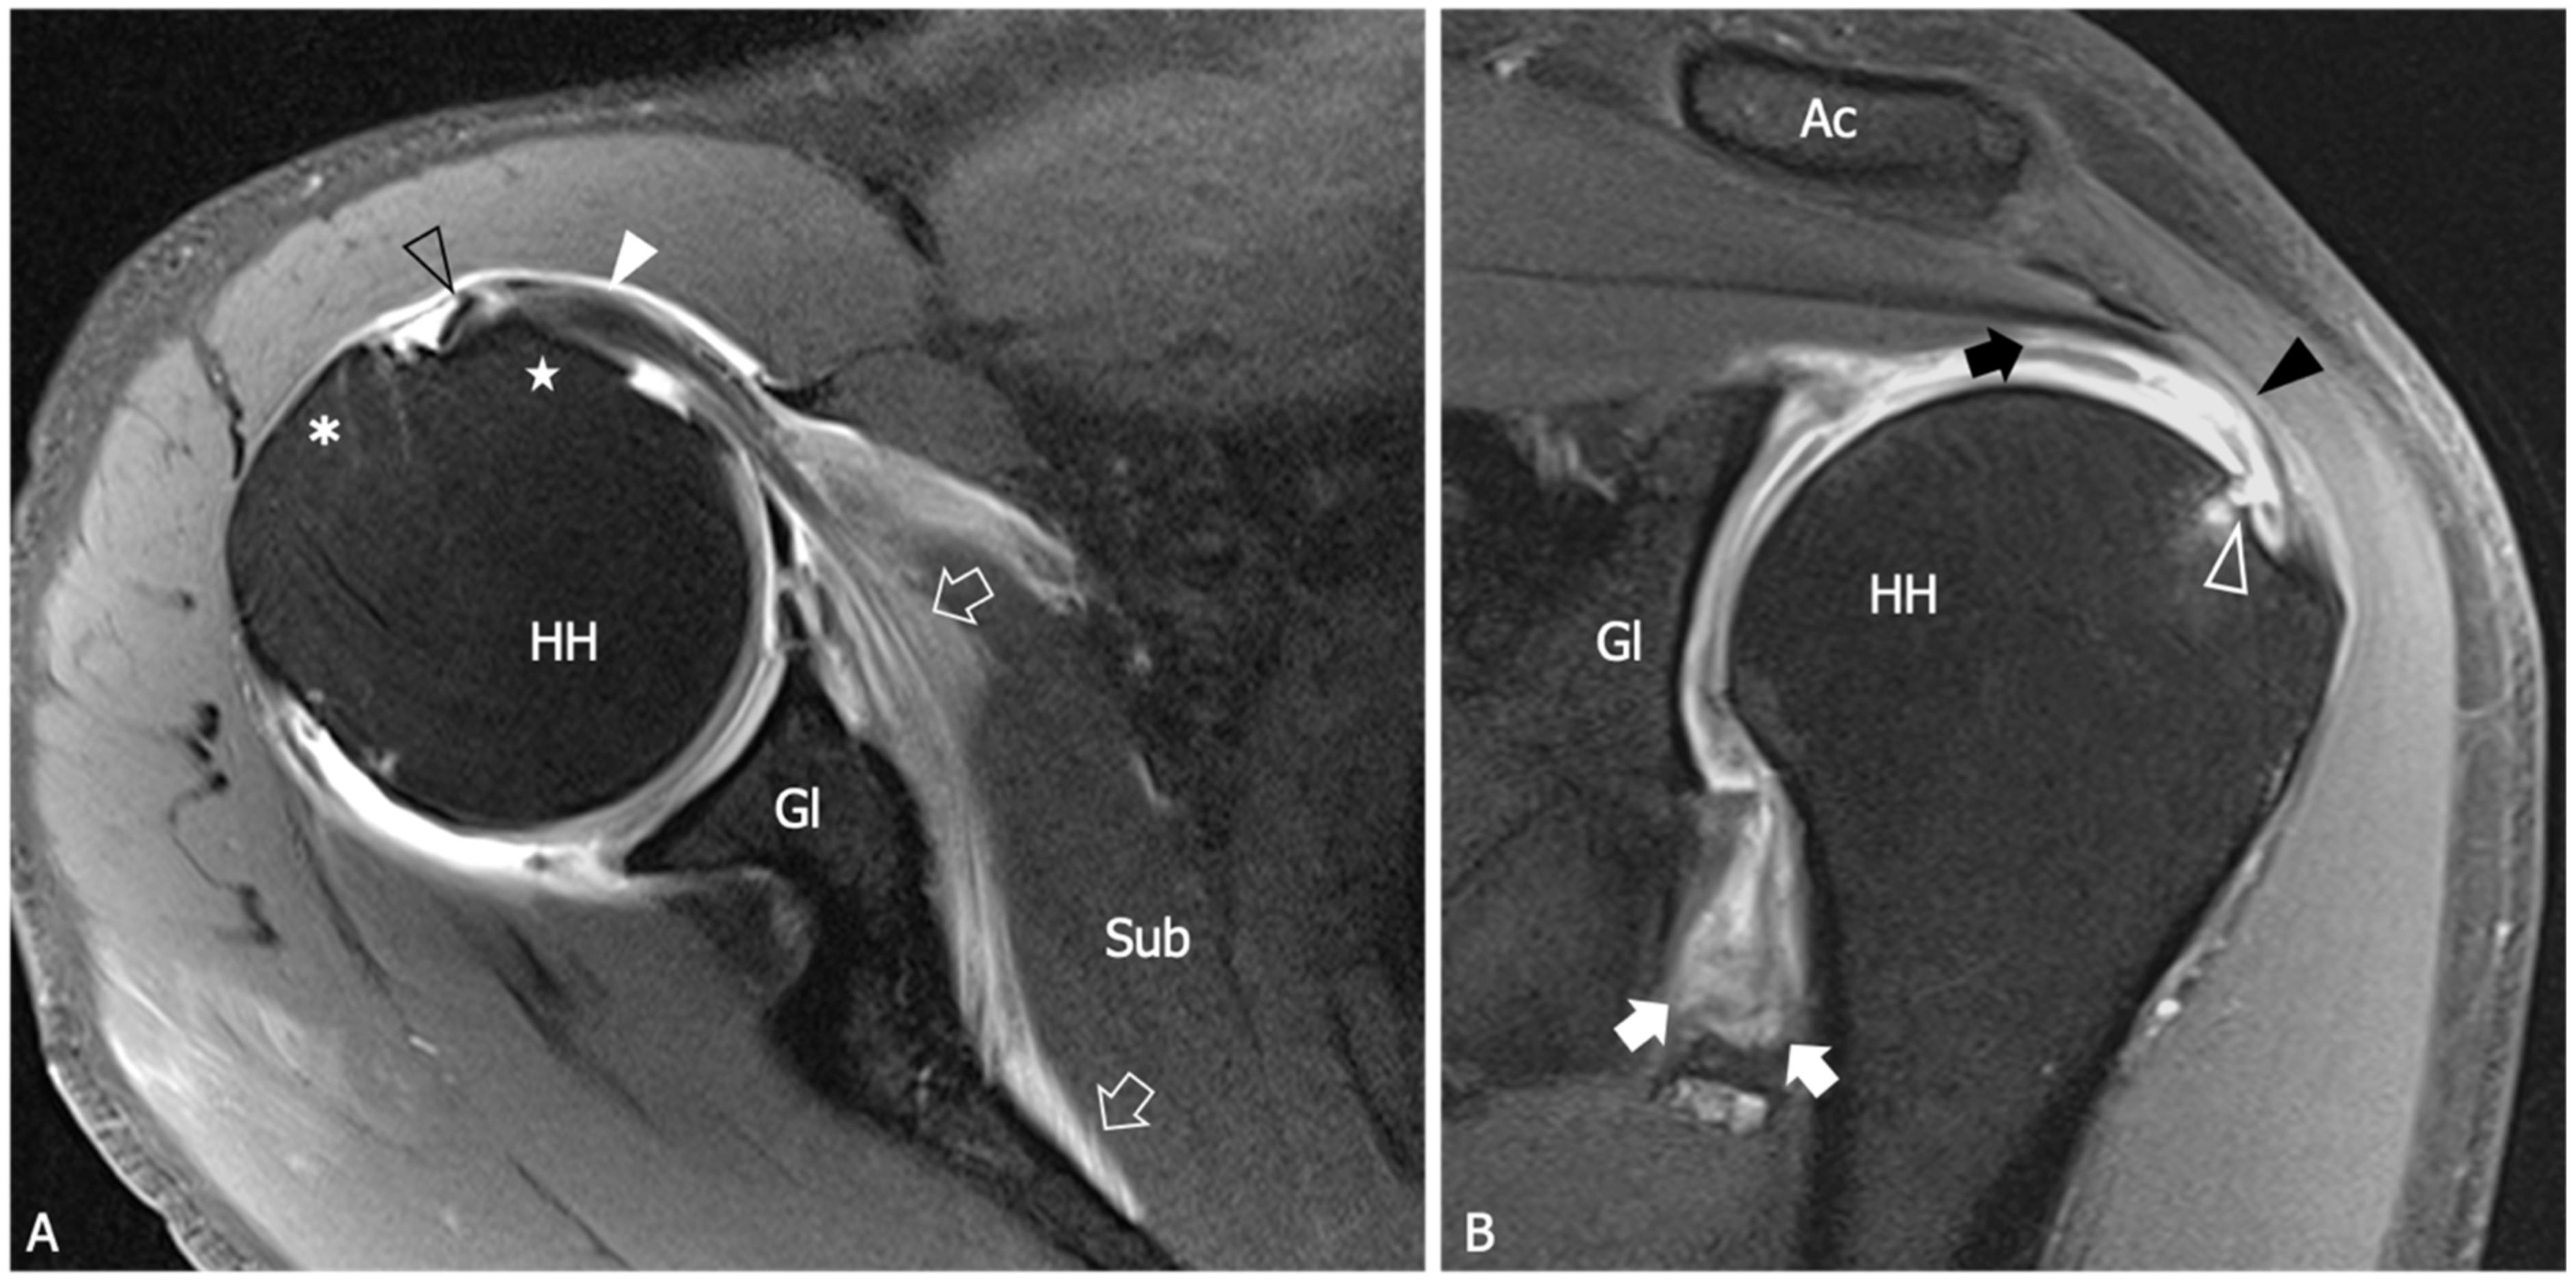

Figure 5.

Glenohumeral joint capsule and pericapsular ligaments, normal US findings. (A) Oblique transverse 18–5 MHz US image shows the normal thin and fibrillar appearance of the coracohumeral ligament (outlined arrowheads), which is demonstrated connecting the coracoid (Co) and humeral head (HH) in a deeper position respective to the coracoacromial ligament (arrowheads). Note the homogeneous and hyperechoic appearance of the subcoracoid fat (asterisk). (B) Short-axis 18–5 MHz US image shows the distal part of the coracohumeral ligament (outlined arrowheads) in the area of the rotator interval and the biceps pulley (asterisk). Bt, long head of the biceps tendon. (C) Longitudinal 18–5 MHz US obtained orienting the probe parallel to the humerus in the axillary region shows the inferior capsule (arrowheads) overlying the humeral head (HH) and folding over the humeral neck (HN).

Figure 6.

US findings in a 53 year old woman with adhesive capsulitis. (A) Oblique transverse 18–5 MHz US image demonstrates the markedly thickened coracohumeral ligament (outlined arrowheads), which has lost the normal fibrillar echotexture and appears homogeneously hypoechoic due to fibrotic changes and degeneration of the fibers. Note the presence of hypoechoic synovial tissue in the subcoracoid triangle (asterisk). Arrowheads, coracoacromial ligament. (B) Short-axis 18–5 Mhz US evidences the thickening and fibrotization of the coracohumeral ligament (arrowheads) and the biceps pulley (asterisks) in the rotator interval. (C) Longitudinal 18–5 MHz US image shows a significant thickening of the inferior capsule (arrowheads). HH, humeral head; Co, coracoid; Bt, long head of the biceps tendon; HN, humeral neck.